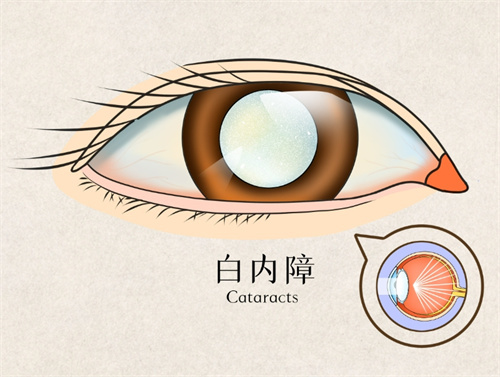

若需联合白内障手术,总费用增至2-5万元。术后半年复查约需2000-4000元。